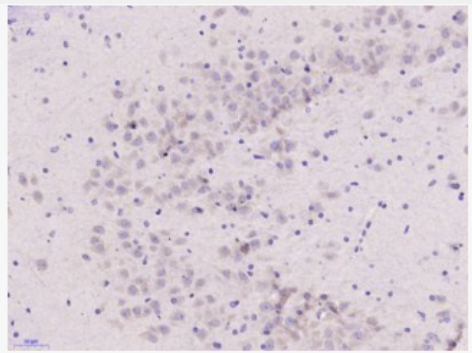

- WB=1:500-2000 IHC-P=1:100-500 IHC-F=1:100-500 (石蜡切片需做抗原修复) not yet tested in other applications. optimal dilutions/concentrations should be determined by the end user.

- WB=1:500-2000 IHC-P=1:100-500 IHC-F=1:100-500 (石蜡切片需做抗原修复) not yet tested in other applications. optimal dilutions/concentrations should be determined by the end user.